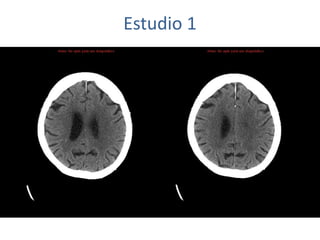

Estudio 1